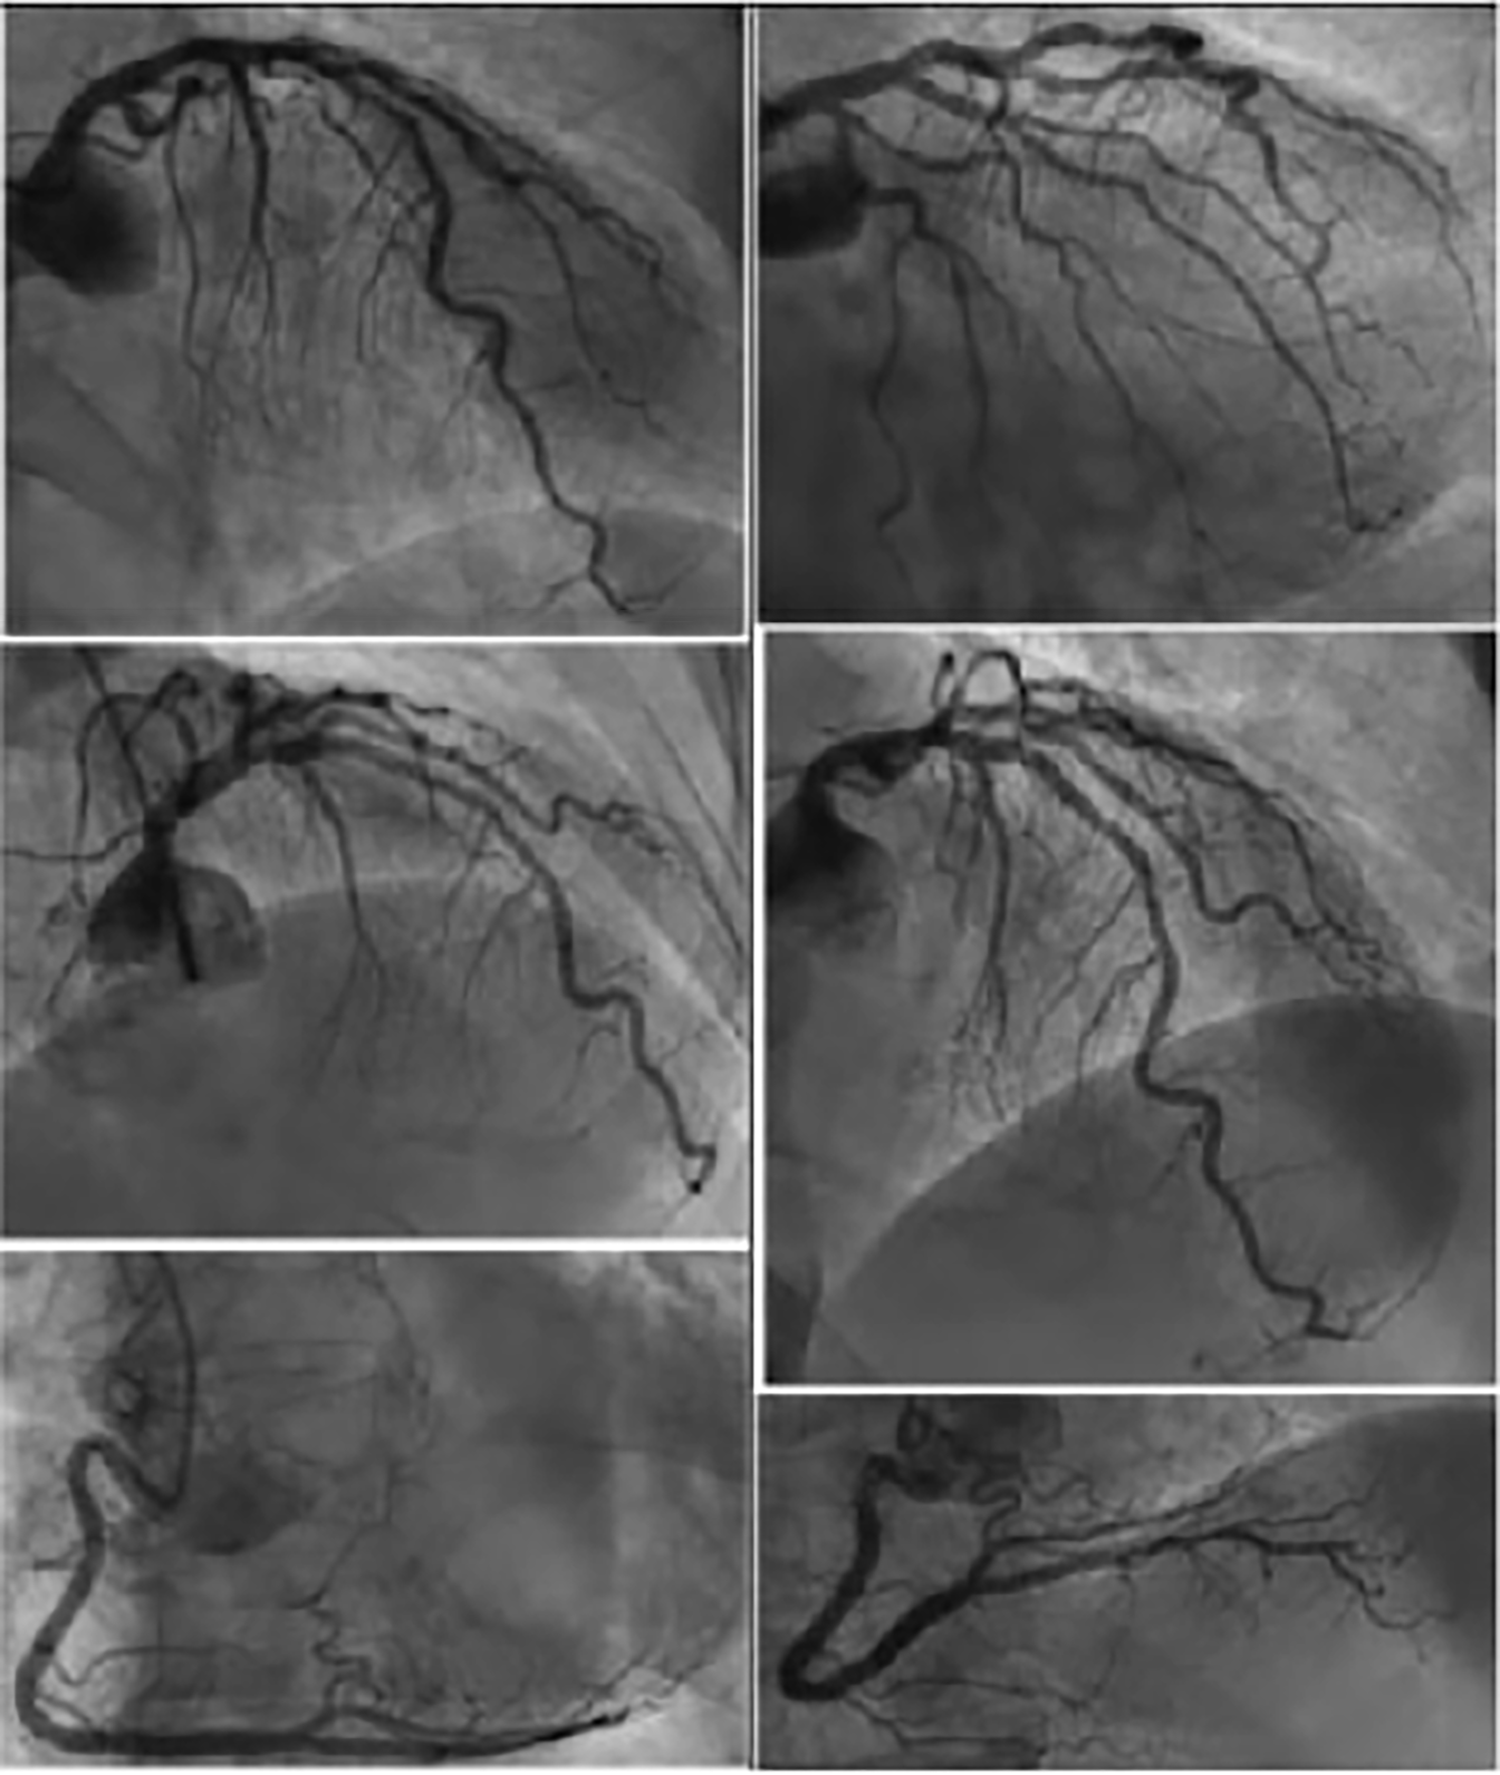

Figure 3

Coronary angiography from patient no.1 showing discreetly atheromatous coronaries.